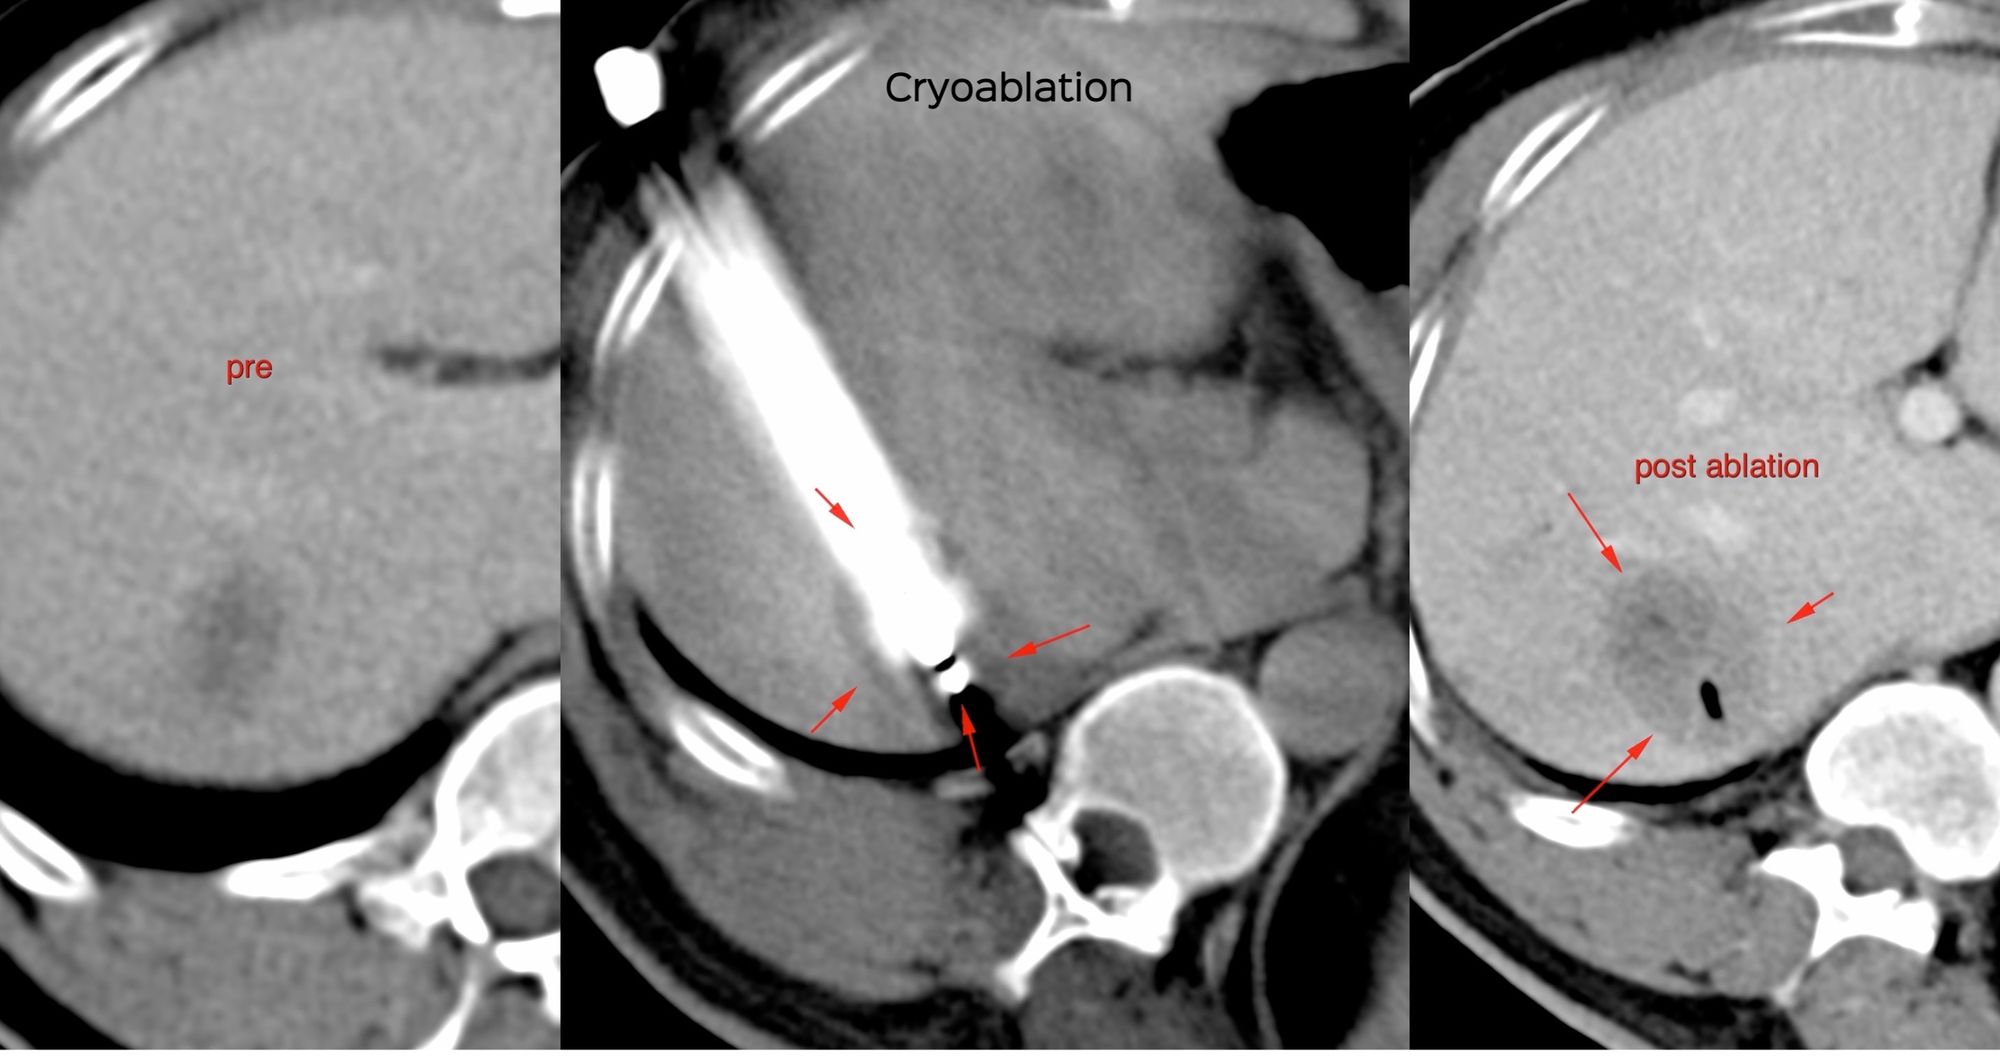

Case 52: Cryoablation of Liver Metastasis

Bhavin Jankharia - 02 August 2021